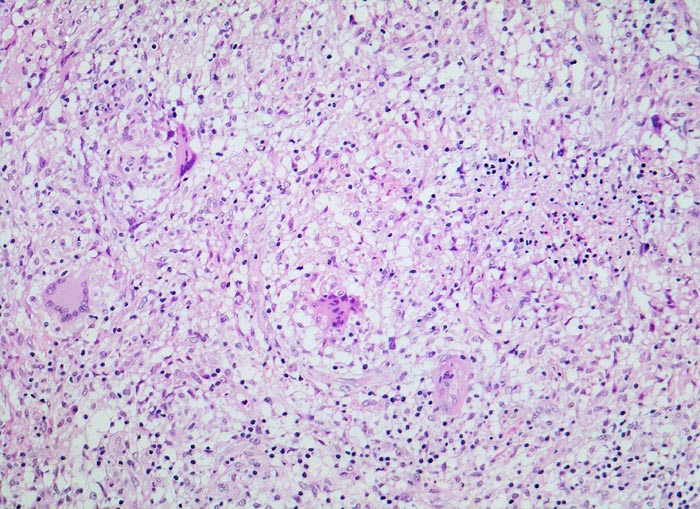

• Girlandenförmige basophile Nekrosezonen durchsetzt von neutrophilen Granulozyten (abszedierende Entzündung).

• Demarkierung der Abszesse durch palisadenförmig angeordnete epitheloide Histiozyten (heller Randwall um die Abszesse).

• Vereinzelt mehrkernige Riesenzellen im histiozytären Randwall.